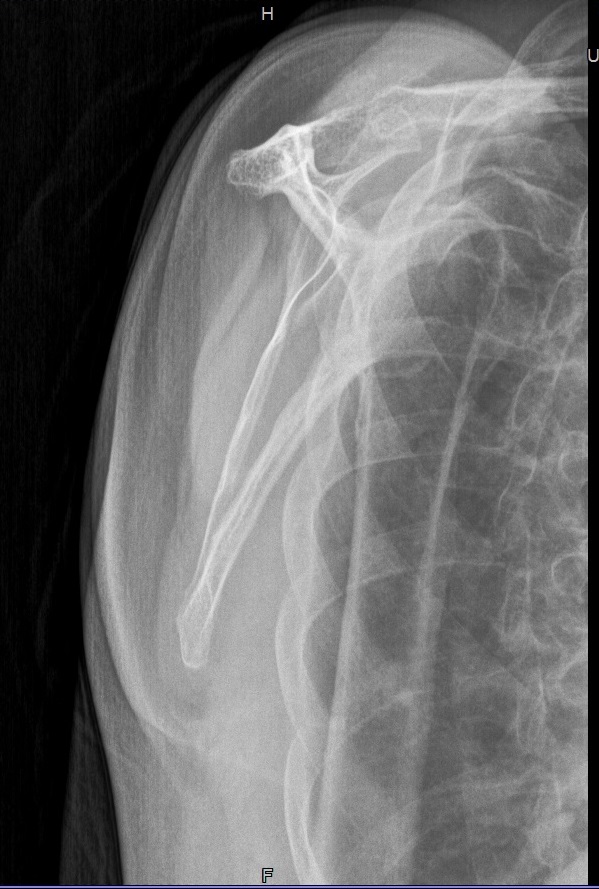

Scapula tangential

36_2.jpg

Fehler

Der häufigste Fehler ist die teilweise Überdeckung der Scapula, vor allem ihres medialen Randes, durch das Rippengitter.

Abhilfe

Patienten bitten möglichst aufrecht zu Sitzen und die Hand gut in Pronation bringen. Beide Scapularänder sind so gut zu Tasten und können so dann in den Profilstrahlengang gedreht werden.